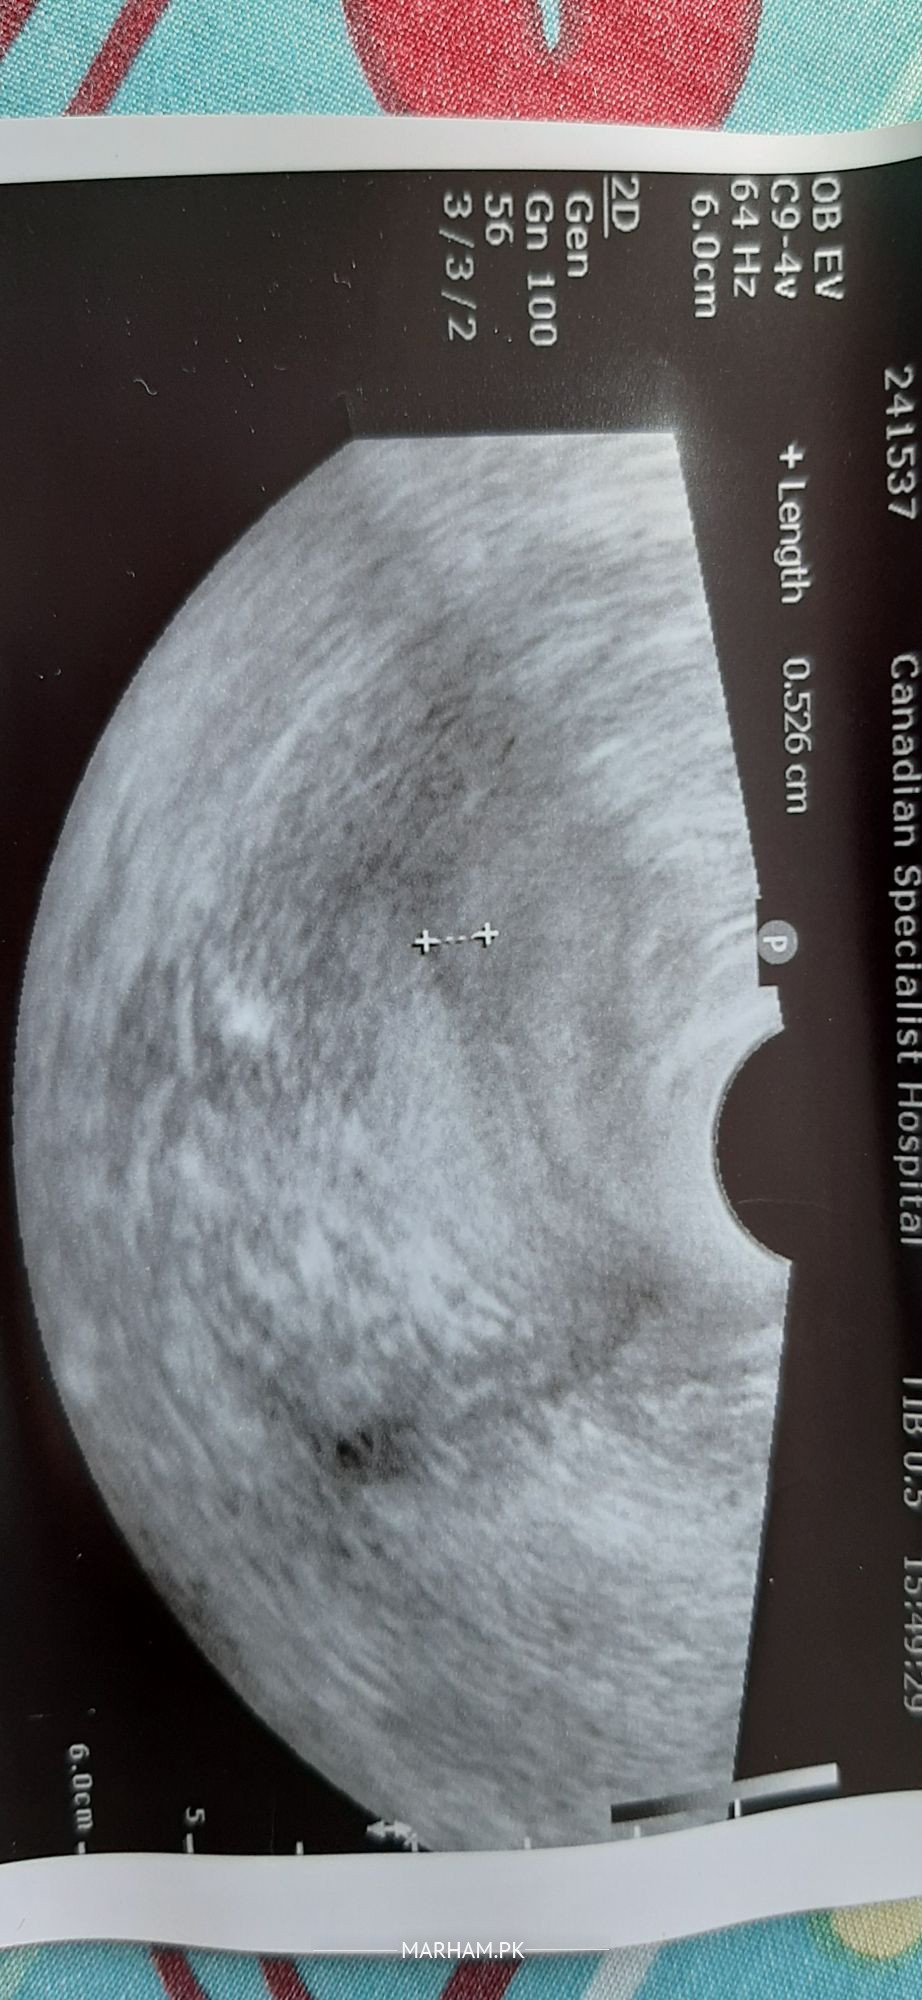

i have done Tvs on 7th day of cycle after a month of DnC. can you please explain my both ovaries are normal or polycystic? what is in utrus?? 2 picture are of ovaries one is of utrus. there is an arrow in my utrus what is it? please tell me my egg sizes on 7th day of cycle is normal or small.

your ovaries normal.no pcos and arrow shows thikening of lining of uterus